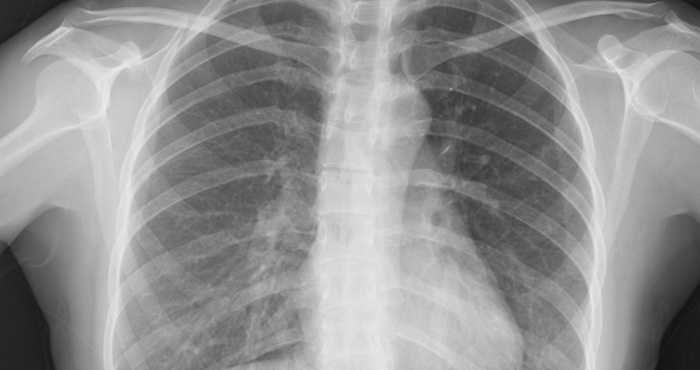

Ảnh y khoa (năm 1895)

Chụp X-quang là kỹ thuật chẩn đoán hình ảnh y khoa đầu tiên trong lịch sử. Năm 1895, nhà vật lý học người Đức Wilhelm Conrad Rӧntgen tình cờ phát hiện kỹ thuật này khi đang thí nghiệm cho dòng điện qua các ống tia âm cực. Chỉ qua một đêm, phát hiện của ông đã thay đổi hoàn toàn ngành y học. Năm 1896, bệnh viện Glasgow mở khoa X-quang đầu tiên trên thế giới.

Siêu âm được đưa vào khoa chẩn đoán hình ảnh từ năm 1955. Các bác sĩ dùng sóng âm thanh tần số cao để tạo ra hình ảnh kỹ thuật, hỗ trợ chẩn đoán bệnh.

Năm 1967, kỹ thuật chụp cắt lớp vi tính (CT) được phát minh, sử dụng tia X và máy tính để chẩn đoán nhiều loại bệnh khác nhau. Máy chụp CT trở thành công cụ chẩn đoán quan trọng trong y học hiện đại.

Công nghệ chụp cộng hưởng từ (MRI) được Paul Lauterbur phát minh năm 1973. Dữ liệu cộng hưởng từ hạt nhân tạo ra hình ảnh chi tiết trong cơ thể, phát hiện khối u, u nang, tổn thương não, tủy sống và một số vấn đề về tim, gan.